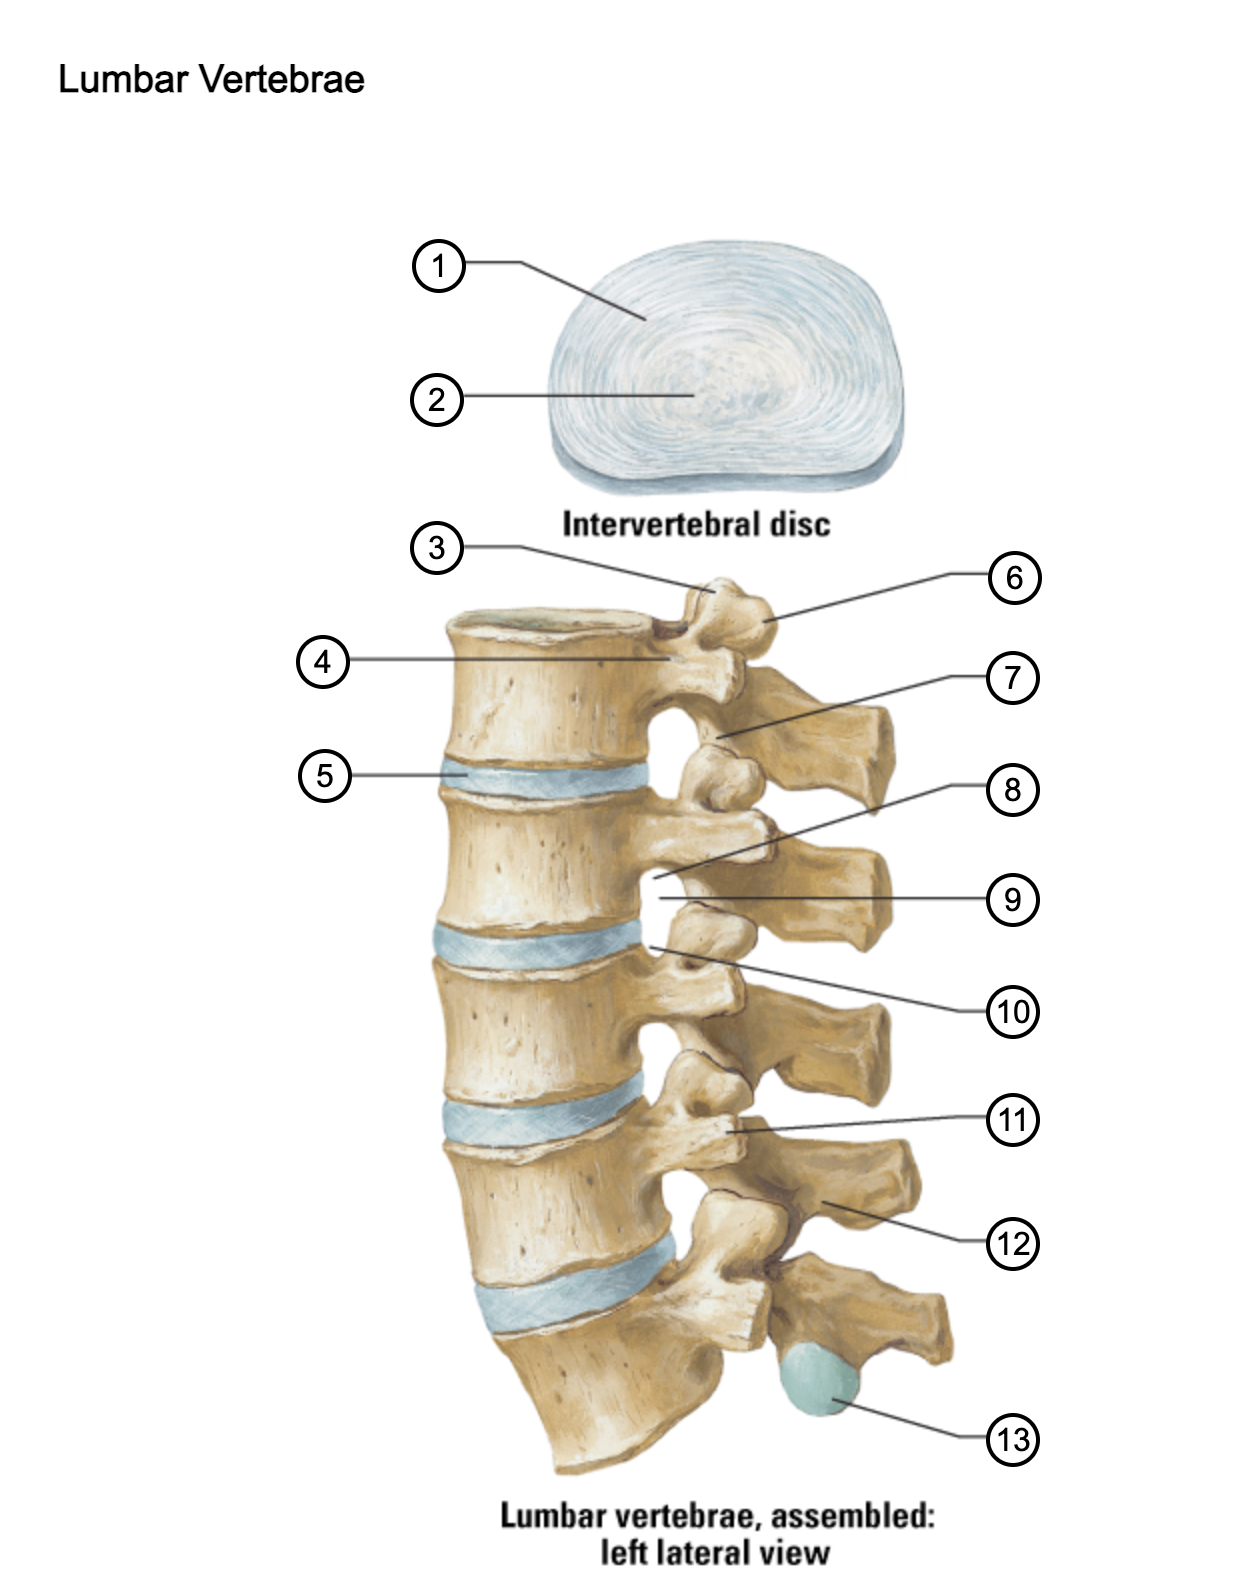

1

anulus fibrosus

2

nucleus pulposus

3

superior articular process

4

pedicle

5

intervertebral disc

6

mammillary process

7

inferior articular process

8

inferior vertebral notch

9

intervertebral notch

10

superior vertebral notch

11

transverse process

12

lamina

13

inferior articular facet